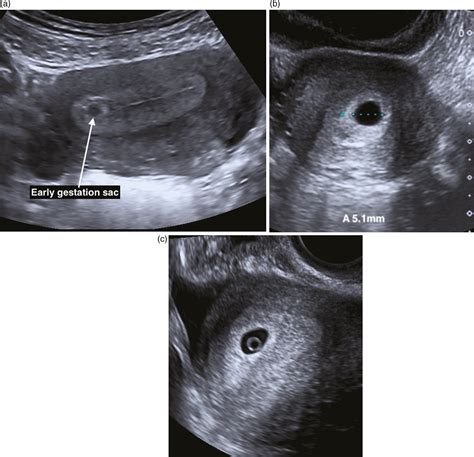

• Gestational Sac: The gestational sac, which contains the developing embryo, should be visible. Its size and location are important indicators of a healthy pregnancy.

• Yolk Sac: The yolk sac, which provides early nutrition to the embryo, should also be visible. Its presence is a positive sign of a viable pregnancy.

• Fetal Pole: The fetal pole, which is the earliest visible part of the embryo, should be visible. It appears as a small, curved structure within the gestational sac.

• Heartbeat: The fetal heartbeat should be detectable and visible on the ultrasound. This is a reassuring sign of a viable pregnancy.